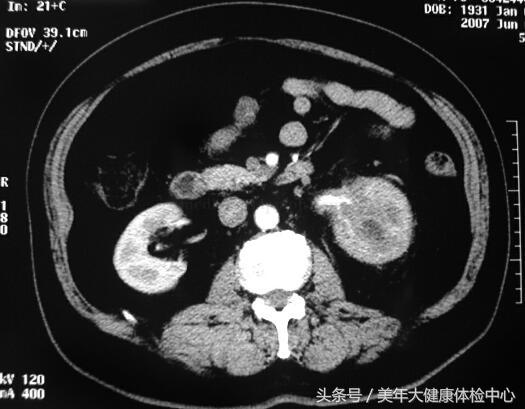

CT(图13-1):平扫左肾中上极病变,肾皮髓质分解不清、包膜不锐利,肾周脂肪囊增厚,左肾门肾盂结构不清,左输尿管上段实变。增强扫描病变无明显强化,病变边界不清。

图13-1 CT平扫